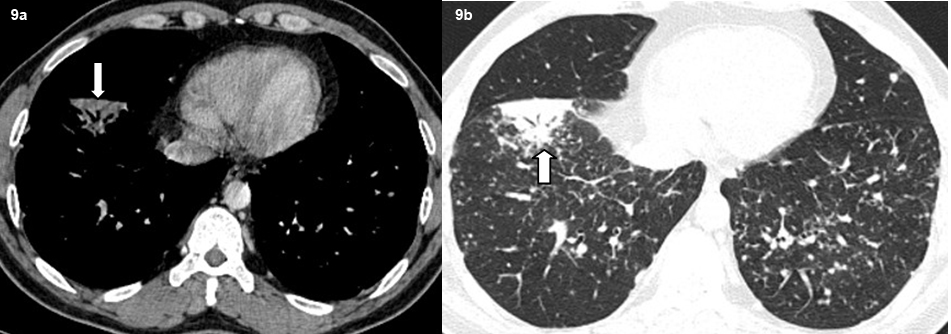

Axial high resolution CT images show subsegmental consolidation with air bronchograms (bold arrow).

A total of 32 patients had lung parenchymal lesions excluding end stage lung disease [Table/Fig-5]. The lung parenchymal findings were classified as being typical or atypical. The most common typical finding seen in 26 patients was micronodular opacities (1-3 mm in size) in a perilymphatic distribution. Perilymphatic distribution included nodules in the peribronchovascular distribution, subpleural regions and nodules along the interlobular septum. Perilymphatic distribution was most commonly appreciated in the parahilar regions and was seen as thickening and nodularity of the peribronchovascular interstitium and in the subpleural locations adjacent to the fissures [Table/Fig-6]. Areas of coalescing of the micronodules into larger nodules of varying sizes were seen in most cases [Table/Fig-7]. Atypical findings were noted in six patients. These atypical findings included patchy ground glass opacities [Table/Fig-8], focal consolidations and confluent conglomerate opacities [Table/Fig-9]. Findings of mosaic attenuation and air trapping were seen in three patients. Predominant involvement of the upper and middle zones was seen in 31 patients. In nine patients, the lesions were found involving both lungs in a diffuse manner [Table/Fig-10,11].

Atypical lung parenchymal lesions were noted in a subset of patients 15% (n=06). These atypical lesions consisted of large pulmonary nodules and masses, patchy air space consolidations, patchy ground glass opacities and areas of air trapping and mosaic attenuation. These opacities represent confluent and coalescing nodules in the interstitium or the acini of the lung parenchyma and are seen in 10 to 40% of patients and are often superimposed on the background of the interstitial nodules [1,13,16]. Air trapping is a non-specific finding which may be seen in a number of patients. Mosaic attenuation pattern indicates small airway involvement by granulomas or fibrosis [17,18].